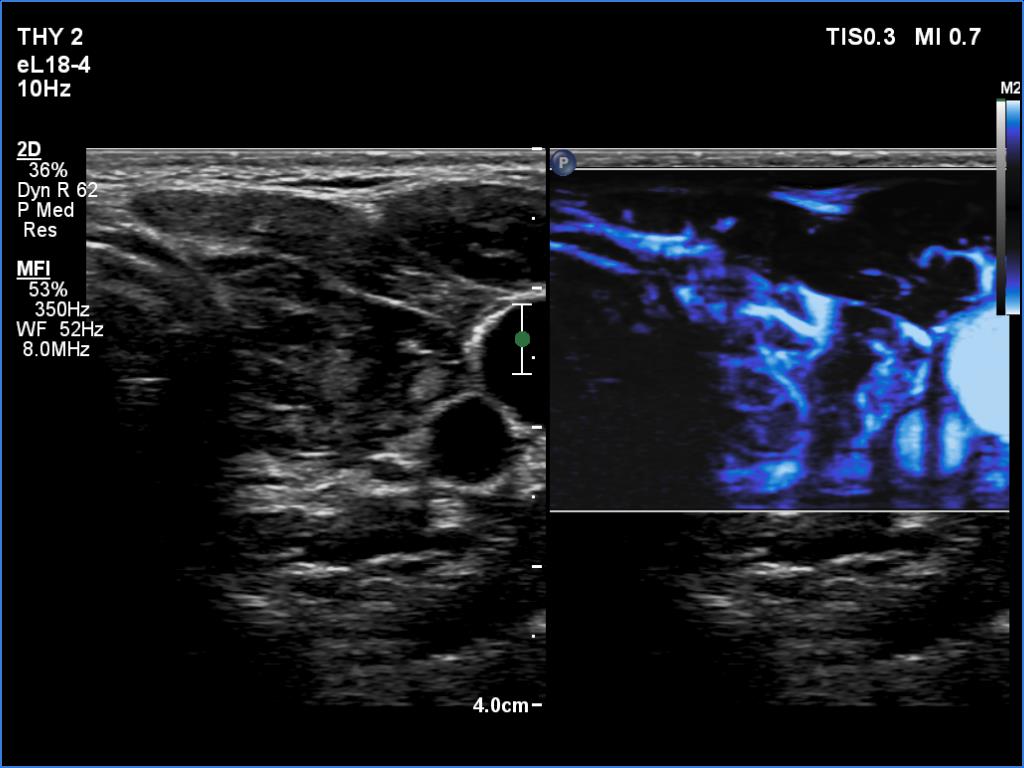

Right lobe, longitudinal scan

Left lobe, transverse scan, microflow imaging. The lobe is rich in vessels.